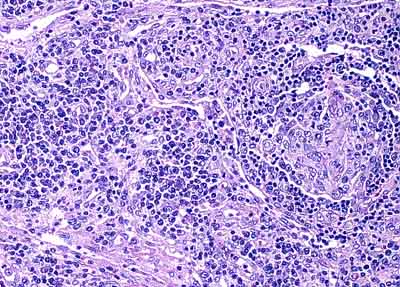

Aids Lymphadenopathy: Follicular Involution

Left: a proliferation of vessels and plasma cells. Right: an involuted follicle |

Left: high power view of involuted follicle with mainly dendritic and endothelial cells remaining. Right: plasmacytosis. |